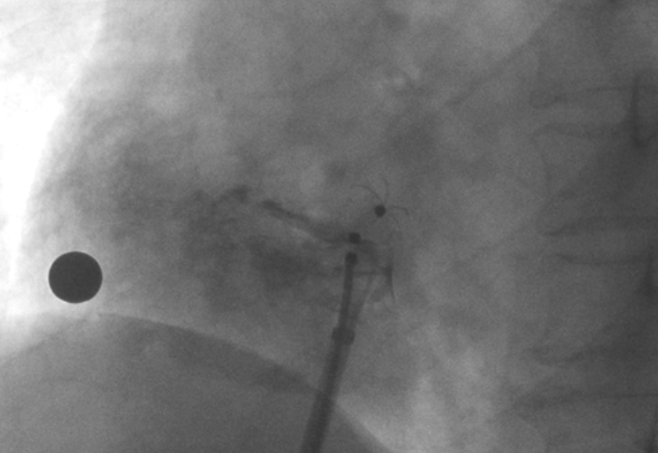

術中造影顯示患者為PFO且長隧道型,目前市場上已商業(yè)化的PFO封堵器難以滿足該患者解剖結構封堵需求。迪創(chuàng)醫(yī)療自主研發(fā)的OmniSeal PFO封堵器自適應性雙盤貼合設計能廣泛適應不同PFO隧道長度的解剖結構和形態(tài),其雙盤外包覆式阻流和隧道內填充阻流相結合的雙重阻流設計,可為此患者實現(xiàn)有效封堵。與此同時,OmniSeal首創(chuàng)的完全可穿刺式設計,也為此患者最大程度地保留了房間隔區(qū)域穿刺通道,以實現(xiàn)全兼容未來可能的左心系統(tǒng)二次介入術。術終造影和心臟超聲顯示封堵完全、效果良好。作為OmniSeal的首例臨床應用,本次手術的順利完成和優(yōu)異效果充分體現(xiàn)了產品的設計創(chuàng)新優(yōu)勢。

造影顯示PFO封堵完全,無殘余分流, 試驗器械充分舒展并貼合良好